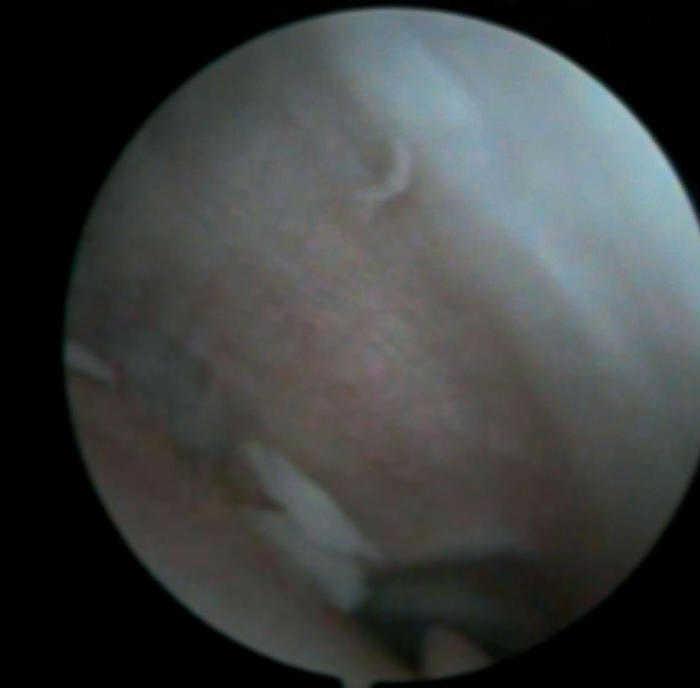

Figura 2 Artroscòpia. Cossos lliures articulars en recessió articular interna.

Es practica una artroscòpia, en la qual s'observen (figs. 2, 4, 6-8):

• Múltiples fragments condrals lliures de vores agudes, que s'identifiquen com recents, i de vores rodones que es cataloguen com antics.

• Lesió condral anfractuosa extensa, amb fragments inestables en cres-ta de la ròtula i en faceta externa, de grau III.

• Resta d'estructures intraarticulars íntegres.

• Es procedeix a l'exèresi dels cossos lliures i la regularització de la lesió condral seguida d'estabilització per vaporització.